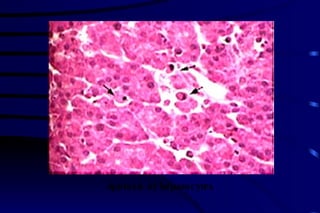

Cytoplasm change:   increased eosinophilium and a more glassy homogeneous appearance and even vacuolated cytoplasm. The Necrosis of heptocytes